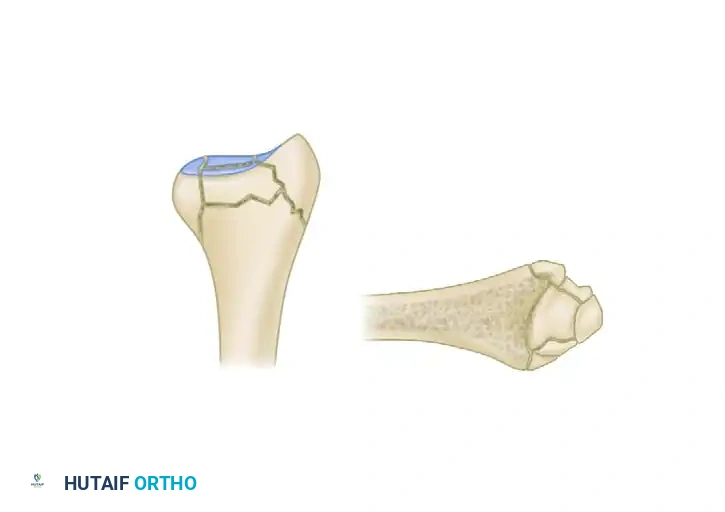

The Five Fracture Fragments

In severe high-energy or osteoporotic distal radius fractures, the bone typically fails in a predictable pattern, resulting in up to five distinct potential fracture fragments:

1. Radial Column (Styloid)

2. Dorsal Cortical Wall

3. Dorsal Ulnar Split

4. Volar Rim (Lunate Facet)

5. Central Intra-articular Fragment

Thin metaphyseal cortical bone does not hold standard screws well. Furthermore, conventional thick plates cannot be applied easily to the dorsal aspect of the distal radius due to the high risk of extensor tendon irritation and eventual rupture. Fragment-specific fixation utilizes low-profile wire-forms and pin-plates to capture these specific fragments without adding excessive bulk.

Associated Surgical & Radiographic Imaging